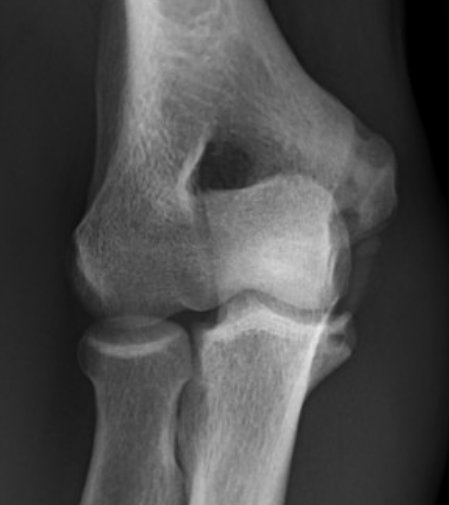

Anatomy of Ulna Collateral Ligament (UCL)

Provides valgus stability

Three components

| Anterior band | Posterior band | Transverse band |

|---|---|---|

|

Most important Stabilizes from 30 - 90 degrees flexion |

Fan shaped Stabilizes from 90 - 120 degrees |

Does not cross elbow joint Does not contribute to vaglus stability |

| Medial epicondyle to sublime tubercle |

Medial epicondyle to medial semilunar notch of ulna |

Medial olecranon to medial coronoid |

Taut band Mean 6 mm thick |

||